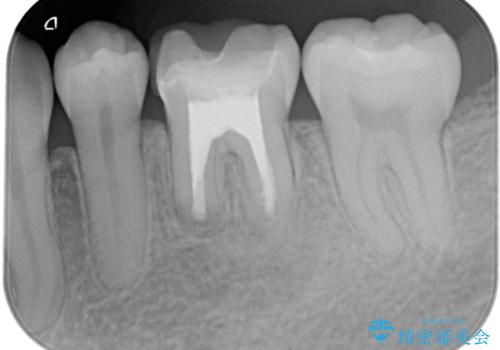

- 昔他院で根管治療を行った歯の病気が再発したことを主訴に来院されました。

レントゲンにて根尖に病変を認め、根尖性歯周炎の診断のもと以下の治療をご提案しました。

外科的歯内療法は根尖性歯周炎の治療における選択肢の一つです。

手術が必要ですが、通常の根管治療では解決できない解剖学的要因も解決できる可能性があります。